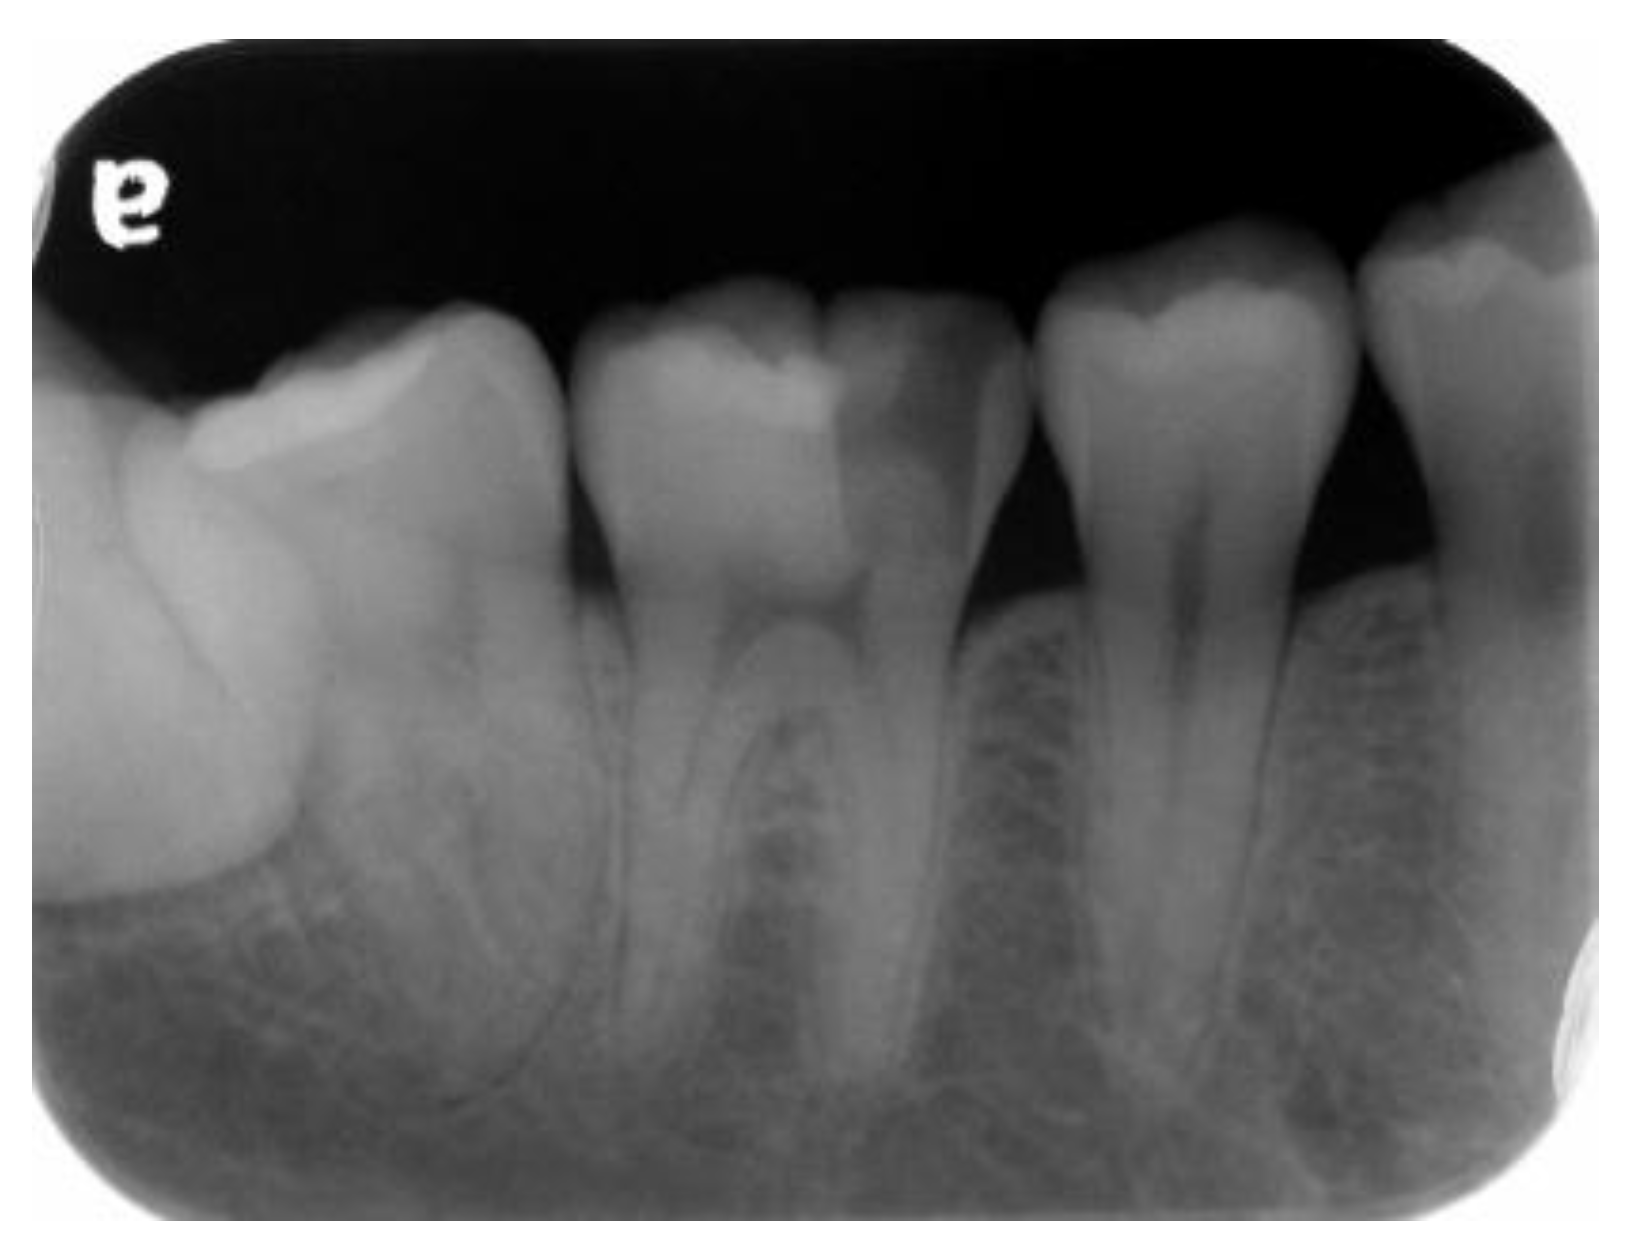

A 22-year-old male student visited the department of restorative and esthetic dentistry of National Taiwan University Hospital for a dislodgement of lower right posterior tooth restoration. He had received direct composite resin filling three years ago, but the old restoration was dislodged while eating popcorn two days earlier. Clinical examination revealed food impaction over the large mesial cavity of the lower right first molar with gingival inflammation (

Figure 1). The pulp vitality test was normal with no symptoms or signs. Radiographic examination revealed a large mesial decay in proximity to the pulp horn while no obvious abnormal apical findings were noted (

Figure 2). After oral hygiene reinforcement, we discussed with the patient that composite onlay might be a choice for his aesthetic and financial concerns, and further possibility of root canal treatment. A written informed consent was obtained before the treatment, and patient gave permission for the related pictures and radiographs to be published before submission.